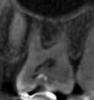

Magdalena Опубликовано 16 декабря, 2012 Поделиться Опубликовано 16 декабря, 2012 С деснами все в порядке, искали карманы - не нашли. З Очень было больно, когда врач пытался засунуть какой-то крючок между 4 и 5 зубами. В этот момент просто привычная ноющая боль становилась нестерпимо ноющей.По томограмме есть карманы в области 24 и 25. Пища в этой области не застревает после еды? Что сказал врач, когда Вы отметили боль при введении инструмента? В области 26 никакой полости под пломбой не вижу по снимку, указывающей на пульпит. Ссылка на комментарий

zadarom Опубликовано 16 декабря, 2012 Автор Поделиться Опубликовано 16 декабря, 2012 Пища застревает и справа, и слева в области 4, 5 зубов. 5-е зубы стоят неровно в дуге, смещены к середине челюсти. Была по этому поводу у ортодонта, который сказал, что это не скученность, а такая особенность, и с ней не надо ничего делать, а тем более если там болит. Пользуюсь зубной нитью, но сейчас уже на больную сторону практически не ем (не потому, что болит, есть как раз не больно, а чтобы не застревала еда и лишний раз не лезть туда ниткой). На мои слова о том, что болит, когда вводят крючок, врач ответил: ну, это, по-видимому четверка, надо удалять нерв. Вот снимок шестерки, крутили ее так и сяк на КТ, вроде нашли полость. Ссылка на комментарий

Magdalena Опубликовано 16 декабря, 2012 Поделиться Опубликовано 16 декабря, 2012 На томограмме, где 4й зуб полостей нет. Не торопитесь депульпировать, рекомендую лечение у пародонтолога - комплекс профгигиены, курс Вектор-терапии, пусть доктор подберет Вам ершики для очищения межзубных промежутков, попробуйте пользоваться дома ирригатором. Боль при введении инструмента, как правило, бывает или при введении в карман или при введении в кариозную полость, т.к. кариеса нет, склоняюсь к карману. Ссылка на комментарий